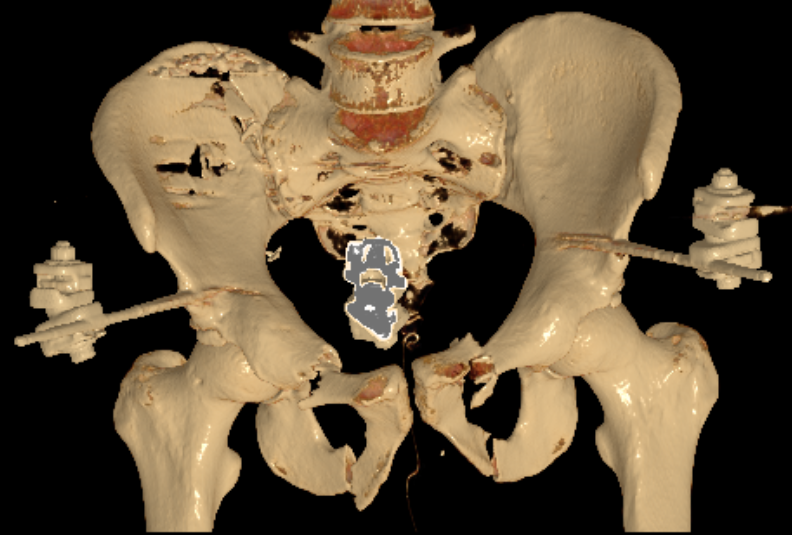

Anterior external fixation to pelvis

Lumbosacral fixation with SI screw - triangular osteosynthesis

Sacral plate, sacroiliac screws, ramus screws

- sacro-iliac screws

- trans-sacral trans-iliac screws

- trans-iliac posterior tension band plating

- lumbosacral fixation